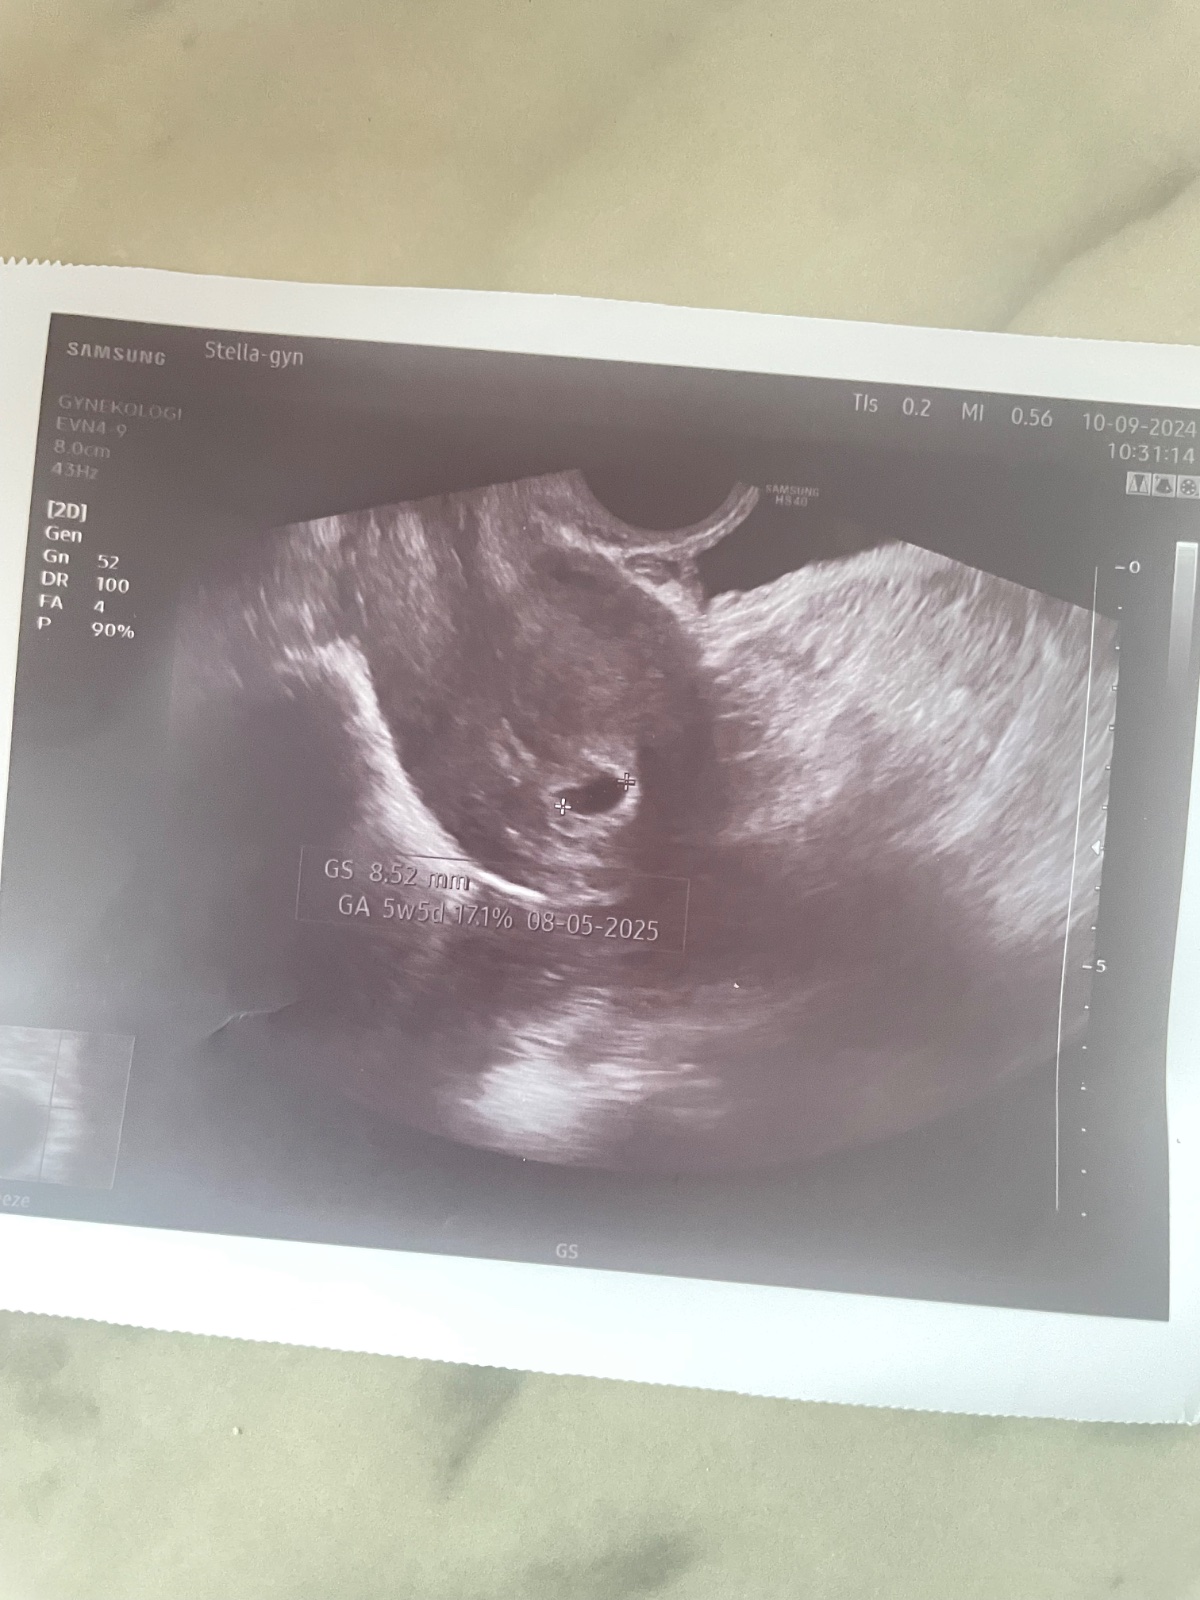

@vlasta1981 holky tak dnes jsem byla na gyndě. Jsem prý 5+5 a neni tam jeste embryo. Ze bud se tam udela nebo ne ☹ co si otom myslite? Posledni ms 29.7.2024 ovulace byla 17den cyklu. V deloze to pry je. Ale zarazilo me, ze pry na hcg vubec nezalezi. Ze dulezity je utz. Co myslite je jeste sance?

@vlasta1981 doufam. 10.9 jdu na prvni utz tak jsem zvedava 🙂